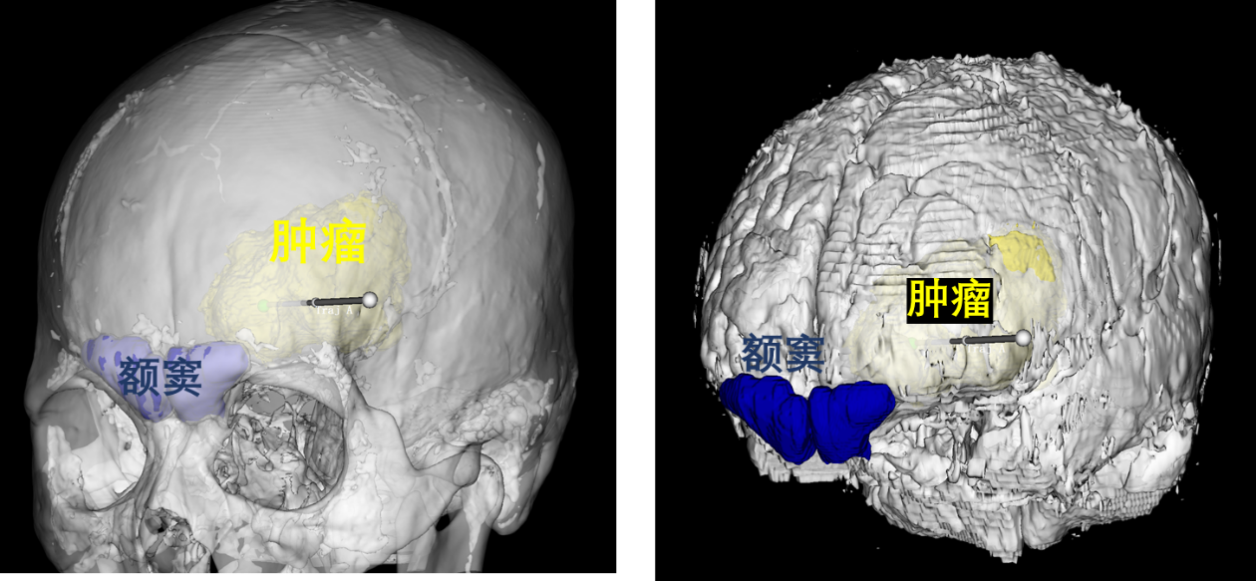

借助三维重建技术,可清晰看到半透明化的头骨和脑组织,肿瘤与头骨上额窦、脑功能区的相对位置一目了然。

左额转移瘤术后第一天复查显示,肿瘤被全切,被挤压的脑室和脑组织成功复位。术后仅 1 周,他便能下地活动,生活实现自理。